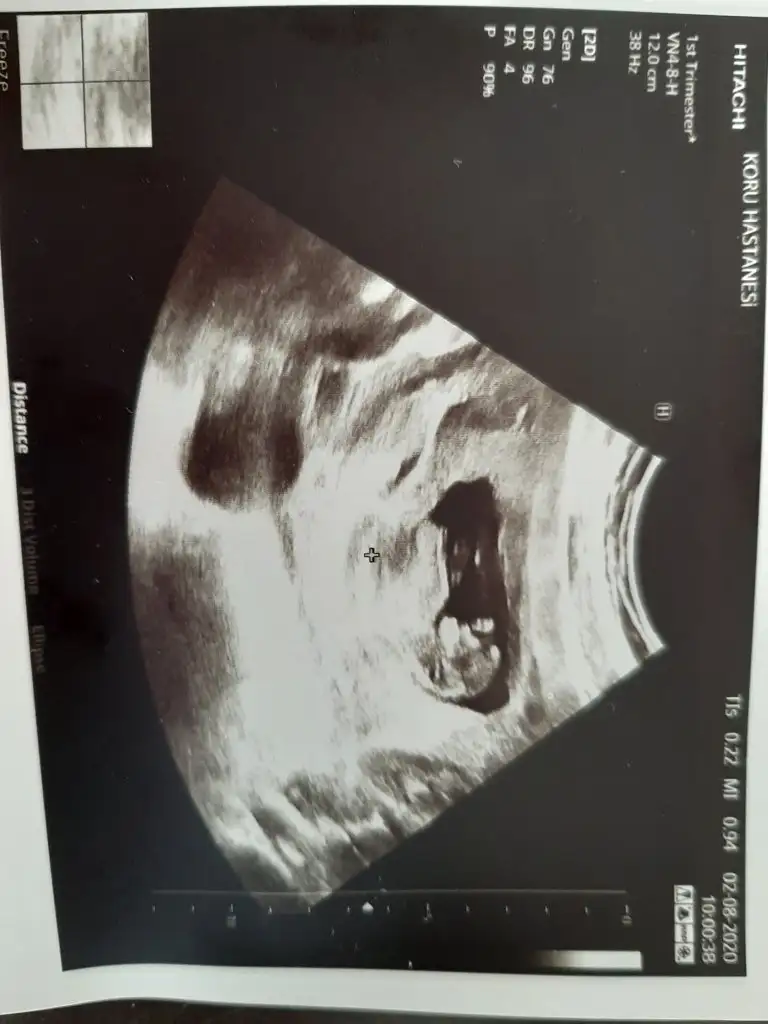

• Screenshot_20200824-122157_Gallery.webp

Screenshot_20200824-122157_Gallery.webp

18 KB · Görüntüleme: 100